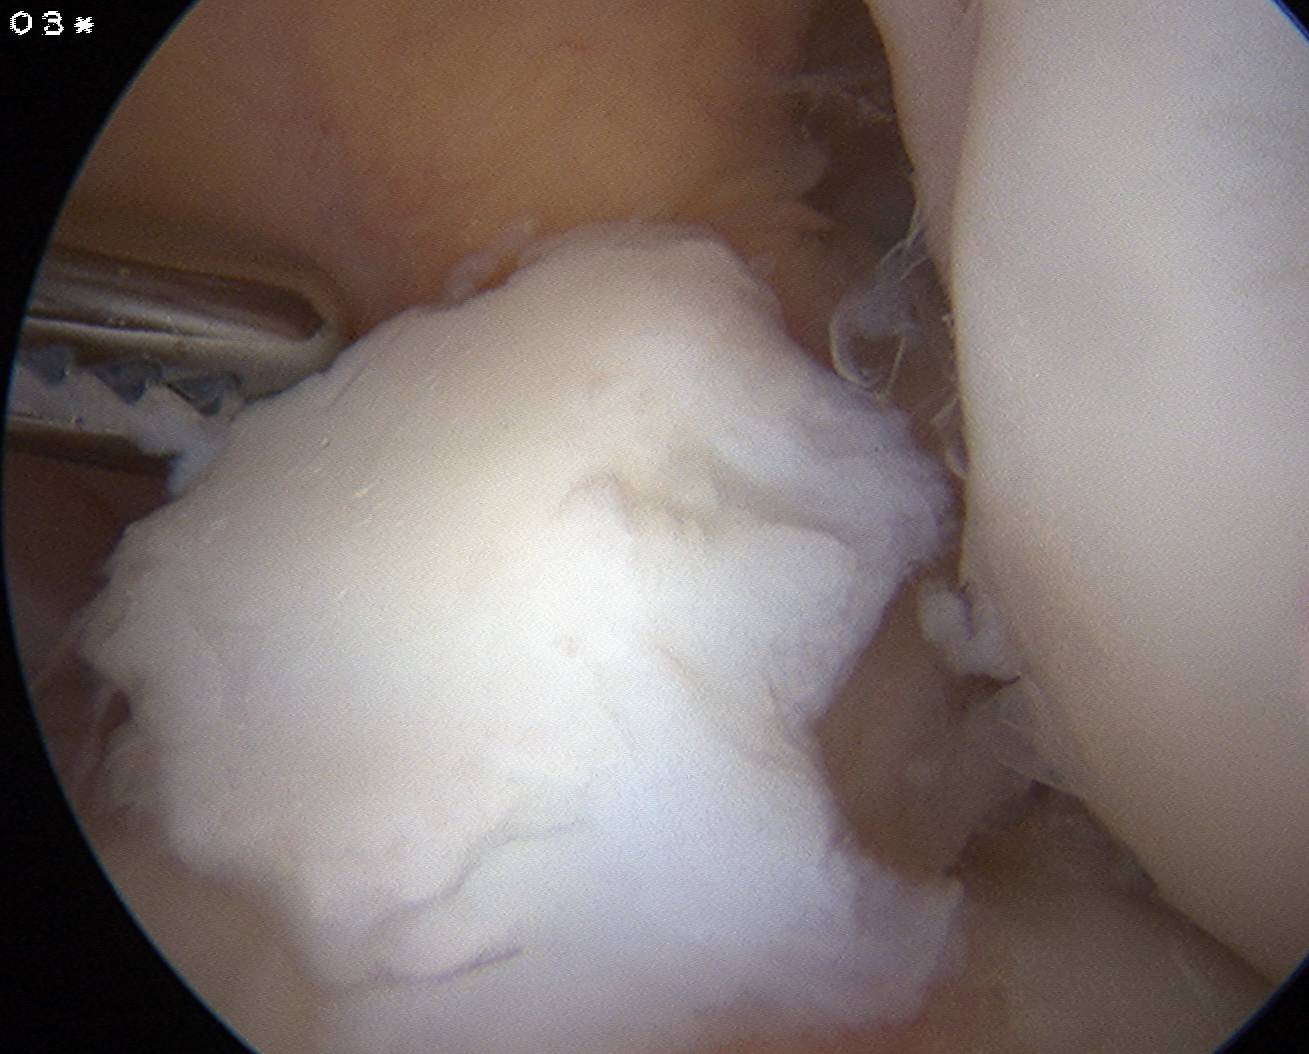

Arthroscopy

Findings

- empty lateral wall

- ACL healed onto PCL

Arthroscopy of left knee showing no ACL attachment to lateral femoral condyle

Arthroscopy of right knee showing no ACL attachment to lateral femoral condyle

Arthroscopy of left knee demonstrating only a few minor fibres attached to lateral femoral condyle